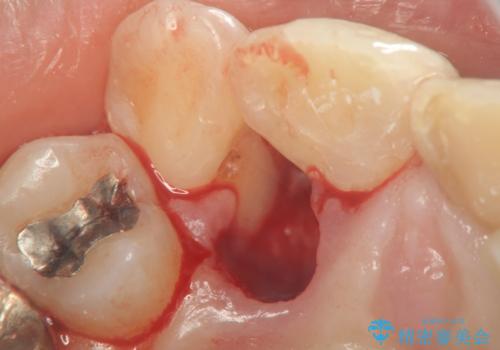

著しいがたつきによる清掃困難 歯牙抜去とセラミック治療

X線写真より、充填剤の突き出た状態の根管治療の再治療を行い、セラミック治療を計画すると同時に、

歯ブラシがしづらく虫歯の原因となっている歯の位置の悪い右上側切歯の抜去を行います。

清掃を難しくしている歯を抜去することで虫歯の再発を防ぐような治療方針としました。